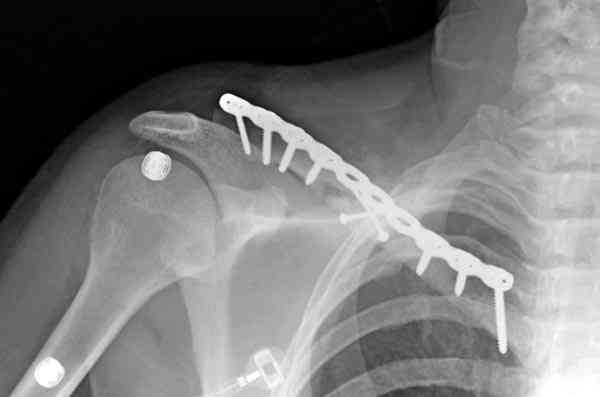

ГГШ> Результат стационарного лечения приведен на рентгенограмме (Xray_3).

Это картинка то есть через неделю после травмы, при выписке? Более чем приемлемо.

Евгений Чекашин: рутинно необходимо выполнение Рг графии в двух проекциях.

С этим трудно спорить, но имеем то, что имеем. Но если в существующей проекции, очевидно, нет контакта между отломками, так ли уж важно второе изображение? Даже если на нем мы увидим проекцию отломков друг на друга и по такой картинке кто-либо будет доказывать, что контакт есть?